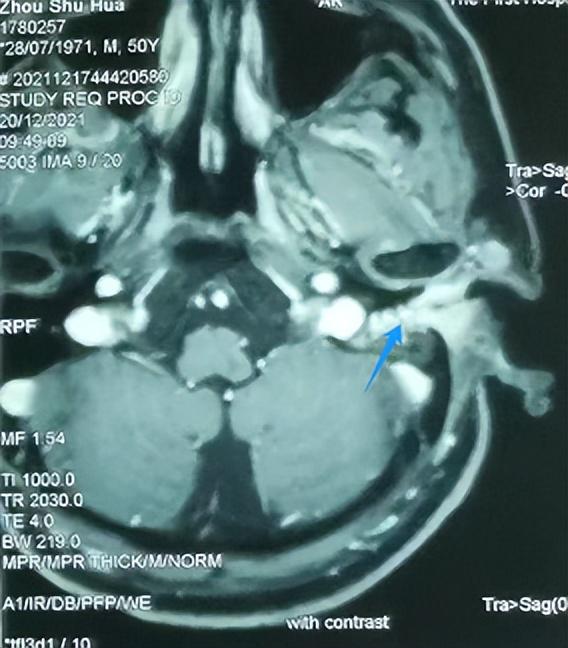

外耳道肿瘤一例! - 好大夫在线